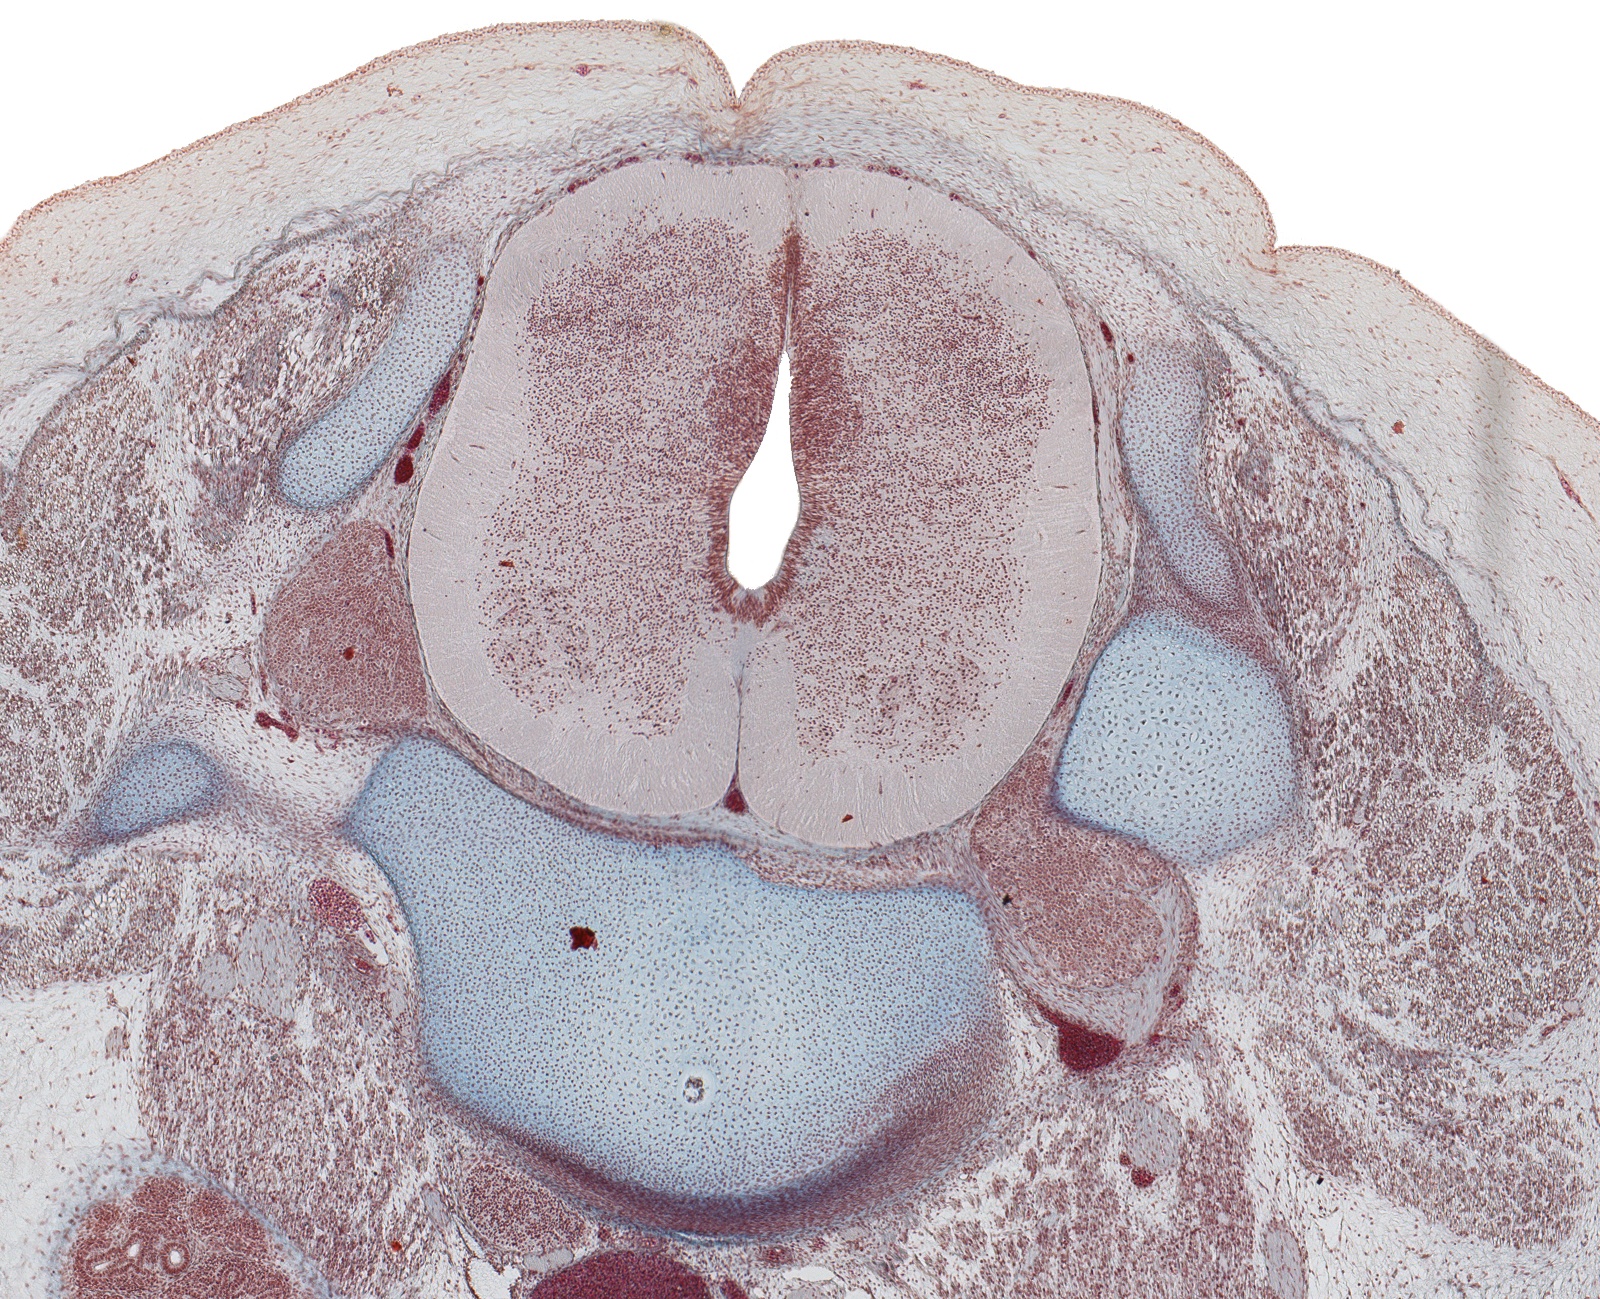

L-3 Spinal Cord and Vertebra

Carnegie Embryo #9226

185-01-01